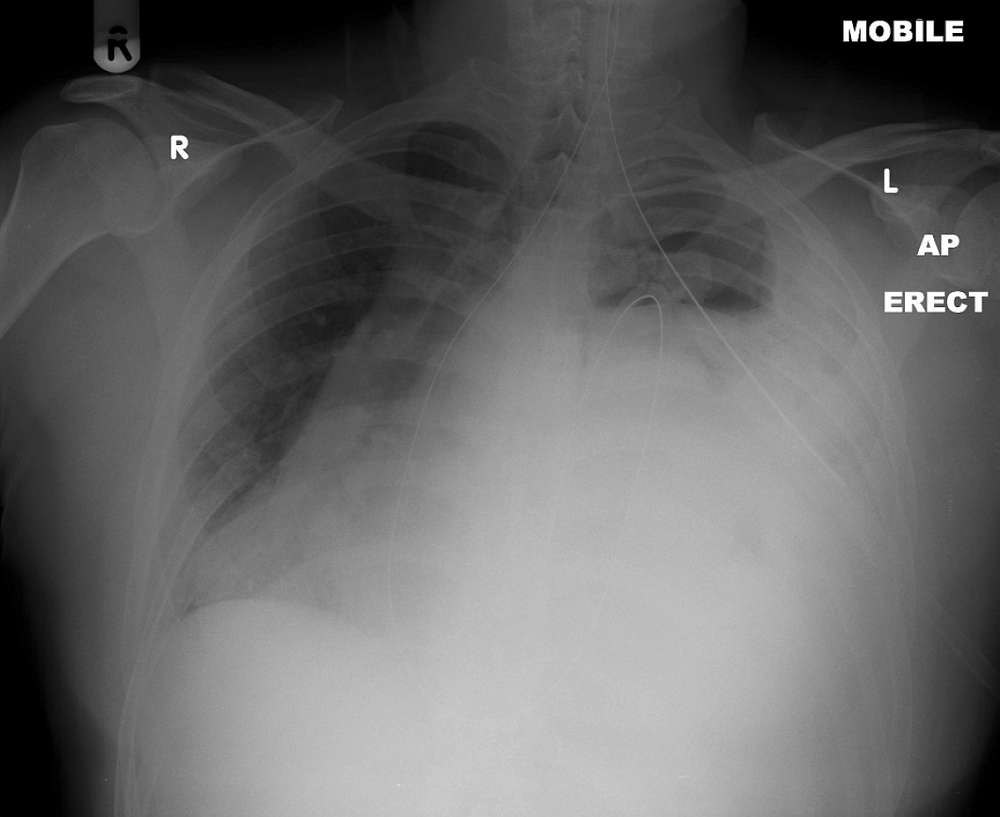

Chronic haematothorax was suspected but multi-detector computer tomography (MDCT) of the thorax confirmed a large left sided diaphragmatic defect with herniation of abdominal contents.

Elective repair was scheduled but the patient presented with acute abdominal pain and type 1 respiratory failure (Pa02 of 7.1kPa with Fi02 of of 60%). Gastric volvulus was diagnosed clinically and decompressed with nasogastric tube insertion. Definitive surgical repair occurred several days later.